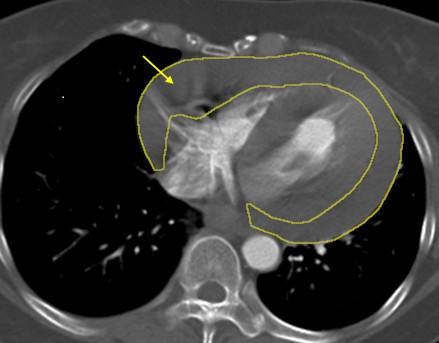

46歲的陳小姐日前騎機車返家途中,突感頭暈、意識不穩而失控摔倒,緊急送抵土城醫院時已陷入休克狀態,急診醫療團隊立即啟動重症評估與影像檢查,經電腦斷層掃描發現,患者心臟外層已迅速累積大量心包積血,並高度懷疑合併外傷引發的「升主動脈剝離」,屬於死亡率極高、分秒必爭的致命急症,隨即啟動跨科整合搶救機制,在關鍵72小時內接力完成三次重大手術,成功將患者從生死關頭拉回。

土城醫院胸腔及心臟血管外科主治醫師鄭元熙指出,心包積血是指血液在極短時間內大量堆積於心臟外層空間,造成心臟受壓,無法正常擴張與跳動,血壓會急遽下降,甚至在數分鐘內引發心跳停止,是典型的立即致命急症;而升主動脈為全身最粗大的血管,一旦發生剝離或破裂,出血速度宛如水管爆裂,臨床上不乏患者在尚未送醫前即發生致命後果。

陳小姐回憶自己長期有反覆頭暈的困擾,過去也曾因突發頭暈騎腳踏車摔倒,但因症狀短暫而未進一步就醫檢查,此次休克後,影像檢查確認為大量心包積血,醫療團隊第一時間成立跨科搶救小組,由心臟外科緊急執行「劍突下心包開窗術」,迅速解除心臟壓迫、穩定循環。